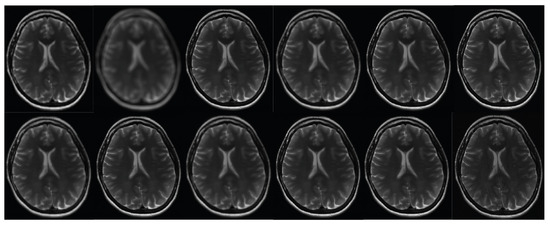

Figure 12. The results of the second phase of the clinical brain imaging trial. This study utilizes the fastMRI test dataset [57]. The current study focuses on the reconstruction of an image using various techniques. In the first row, the regular sampling scheme is utilized without motion correction and with SRR applied (1) (PSNR = 22.89 dB). The reconstruction process involves the use of the B-spline curve (2) (PSNR = 23.22 dB), Yang’s method [50] (3) (PSNR = 26.30 dB), Lim’s method (4) (PSNR = 29.71 dB) as referenced in [20], Zhang’s procedure (5) (PSNR = 28.54 dB) as referenced in [51], and Zhang’s second algorithm (6) (PSNR = 29.77 dB) as referenced in [43]. In the second row, Mahapatra’s method [52] (7) (PSNR = 29.23 dB) and Wang et al.’s [53] procedure (8) (PSNR = 30.21 dB) are employed. Furthermore, the reconstruction procedure utilizes Guerreiro’s approach [54] (9) (PSNR = 30.77 dB), Pham et al.’s method [55] (10) (PSNR = 23.65 dB), Shi’s method [17] (11) (PSNR = 30.80 dB), and the author’s method (12) (PSNR = 34.02 dB) [20]. Furthermore, in order to achieve super-resolution, a suggested sampling strategy and motion correction techniques are employed. The aforementioned procedures are implemented without the inclusion of supplementary data. The compression ratio is 50%.